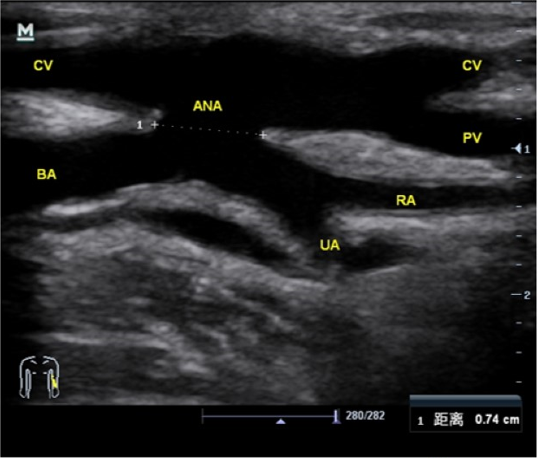

静脉评估

自拟定吻合口至锁骨下静脉,包括浅静脉及其属支、穿支、深静脉静脉直径(2.5-3.0mm)、通畅性、连续性以及可扩张性*

关注解剖变异

关注瓣膜位置

超声提示左上臂肱动脉高分又变异,变异类型:肱桡动脉